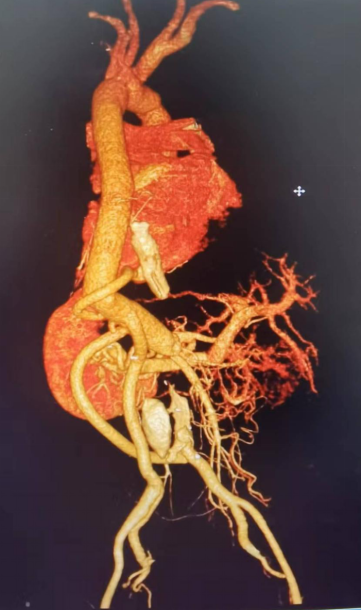

患者术后胸腹主动脉CTA复查结果示重建血管形态良好、各分支重建满意